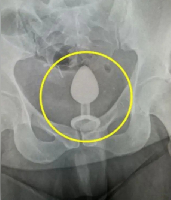

В случае перелома шейки бедра компания МосРентген Центр госпитализирует в Склиф для эндопротезирования.